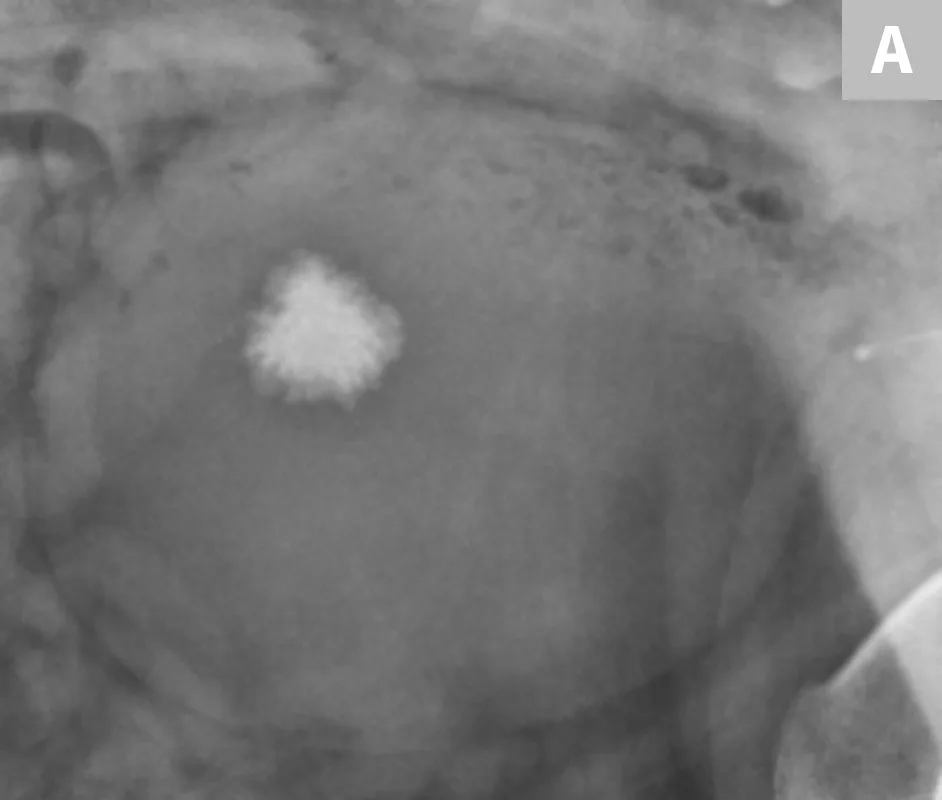

A separate center of ossification associated with the os penis may mimic a urethral calculus (Figure 11 A and B). A separate center of ossification can be seen at either end of the os penis and will be in line with the os penis. A calculus within the penile urethra would be seen ventral to the os penis in the location of the urethra. Contrast urethrography can be a helpful way to differentiate between a separate center of ossification and urethral calculus (Figure 11C).

FIGURE 11A

Lateral radiograph of a male dog collimated to include the urinary bladder and os penis. Note the well-defined mineral opacity just proximal to and at the same level as the base of the os penis—a separate center of ossification (arrow). Also note the two soft tissue opaque nodules summating with the prepuce, presumed to be small nipples (arrowheads).